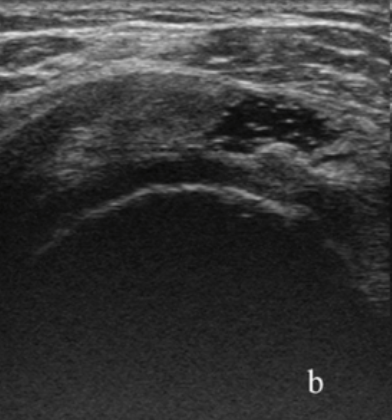

A

Rotura tendon supraespinosos